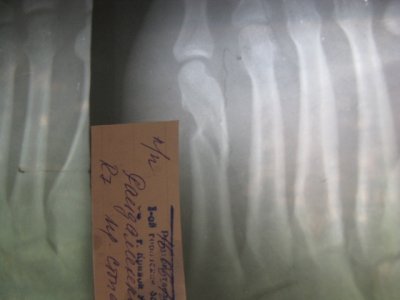

Здравствуйте доктор. Я уже к вам обращался, большое спасибо за ответ, хотелось бы задать еще вопросы... Мне 23 года, у меня закрытый перелом 5-ой плюсневой кости, просидев месяц дома мне сделали второй снимок. Врач снял мне шину, но сказал 2 недели ногу не нагружать. Я переживаю, что перелом вообще не сросся. Я не ем мяса и рыбы, может причины медленного сростания в этом. Я знаю как к вегетарианству относятся врачи, но в любом случае, подскажите пожалуйста, возможно ли поправить ситуацию не начав употреблять мясо? И вообще, буду очень благодарен за любые советы и рекомендации! Еще раз заранее огромное спасибо! Прилагаю фото за 13.01.12 Посмотреть вложение 6101 и за 13.02.12 Посмотреть вложение 6102

Не в мясе дело, это перелом такой непростой. На всякий случай принимайте Дону и начинайте ходить в стельке со стяжкой переднего отдела стопы.